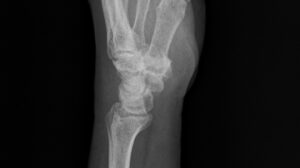

以下の5枚は再発後、手術直前に撮影されたレントゲン写真である。正面像では舟状骨遠位部に骨折線が見え、斜位像および側面像では骨片のずれが明確に確認できる。

/レントゲン写真を角度を変えて5枚撮影

さらに医師は、治療方針として 「骨移植+スクリュー固定術」 を提示した。

骨が癒合しにくい特徴を持つ舟状骨では、骨片を移植して血流を補い、ビスで確実に固定する術式が選択されることが多いという。

説明を受ける中で、再発例としては標準的な対応であることが理解できた。